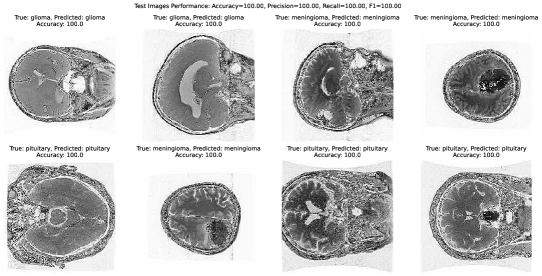

Further, a test performance measurement analysis as depicted in Fig 12 we have also included a measure of our proposal where we provide a performance of our efficient brain tumor classification model by illustrating a visualization of performance metrics for some random images to prove the effectiveness of our model in random input images. The results of the random test images (a total of 8 images) were astonishing, with a perfect accuracy rate of 100% for each image!

Refer to caption

Figure 12: Performance measurements of our proposed model